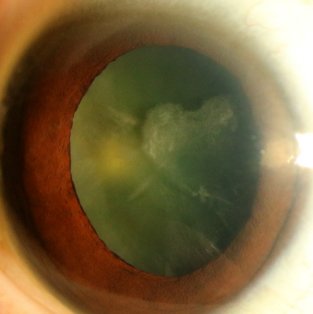

白内障是全球首位的致盲性眼病,老年性白内障是最常见的类型。图1为1例普通皮质型老年性白内障患者术前的裂隙灯照片。散瞳后可见不均匀浑浊的皮质恰好在瞳孔中组成一个爱心的形状。这犹如在告诉我们,虽然行医之路任重而道远,但愿我们眼中有爱,心中有光,目光所及皆是美好。

图1 皮质型老年性白内障裂隙灯照片